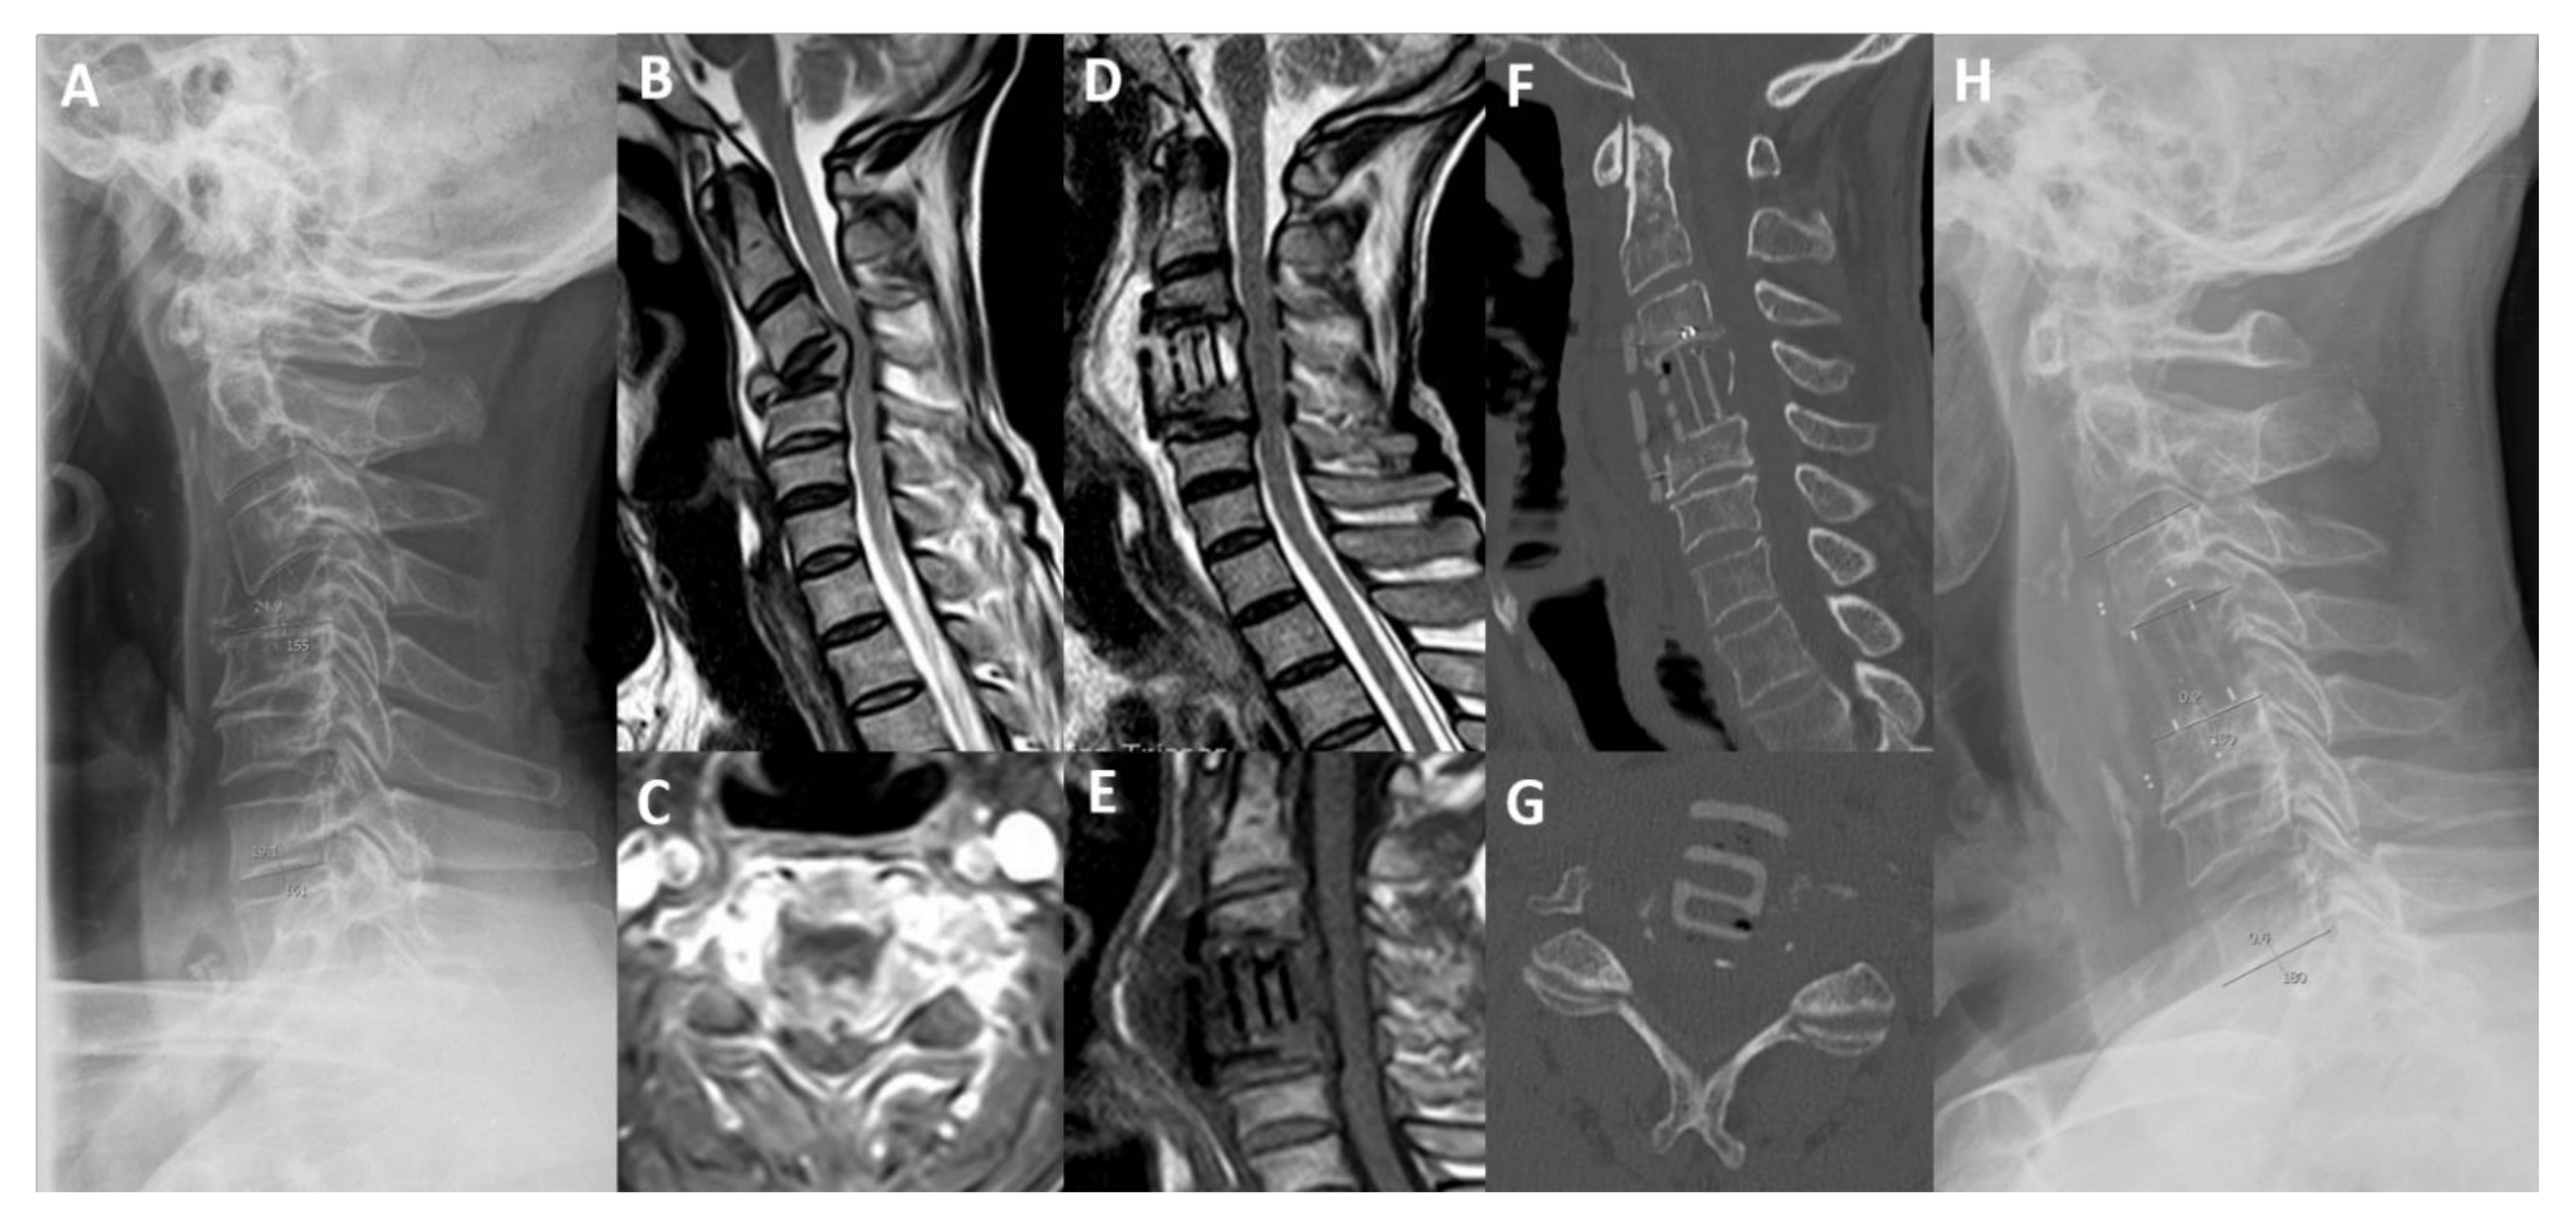

Anterior Corpectomy and Plating with Carbon-PEEK Instrumentation for Cervical Spinal Metastases: Clinical and Radiological Outcomes

2.3. Surgical Technique